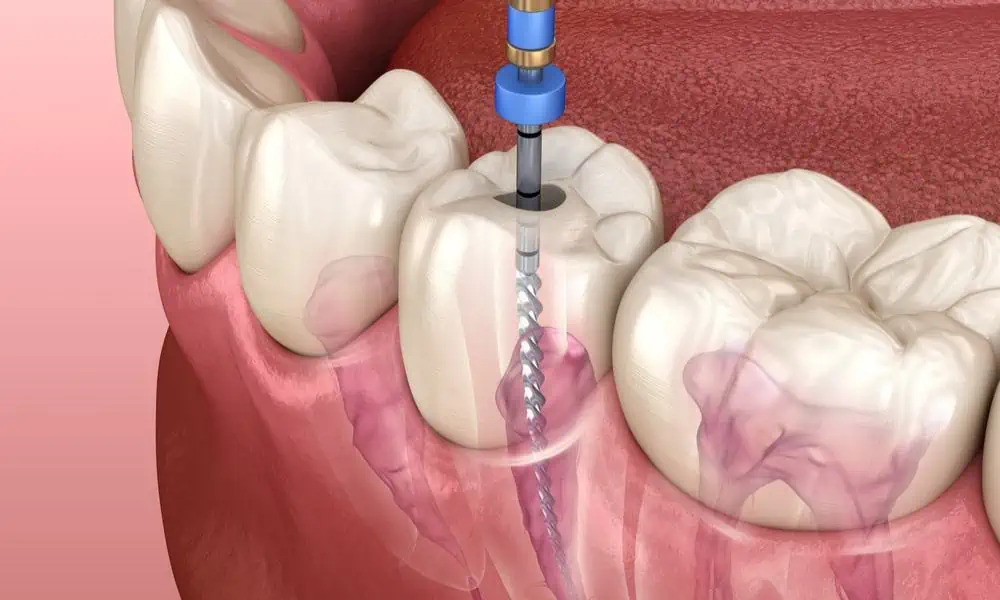

- Pulpektomija: Napravi se otvor u kruni zuba. Bolesna ili mrtva pulpa se uklanja iz pulpne komore i korijenskih kanala.

- Čišćenje i oblikovanje: Male turpije se koriste za čišćenje, proširenje i oblikovanje kanala kako bi se pripremili za punjenje.